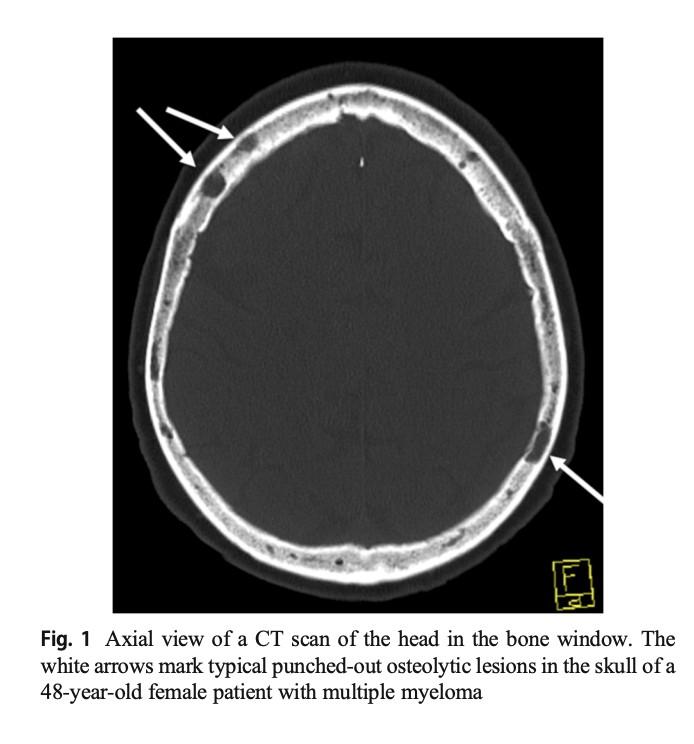

Bone Disease in Multiple Myeloma

Kyle RA. Mayo Clin Proc. 1975;50:29.

• A burdensome and frequent complication in MM

• Present in up to 80% of patients at diagnosis

• Characterized by osteolytic bone lesions secondary to increased bone resorption and impaired bone formation

• Sequelae

• Pathological fractures

• Osteoporosis

• Hypercalcemia

• Bone pain

• Spinal cord compression

Skeletal CT scan

K. Treiti et al. Skeletal Radiology 2021